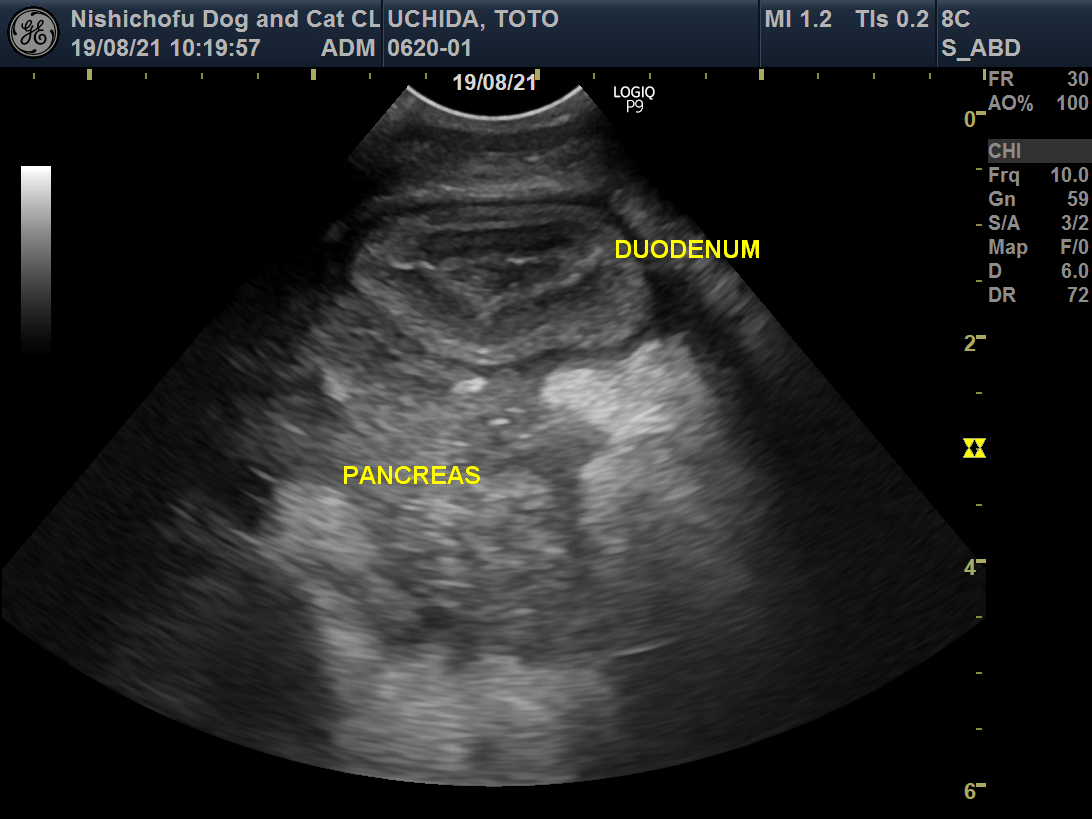

炎症を起こしている膵臓(PANCREAS)。

炎症を起こしている膵臓(PANCREAS)。 正常な膵臓(PANCREAS)

正常な膵臓(PANCREAS) 正常な膵臓(PANCREAS)

正常な膵臓(PANCREAS)